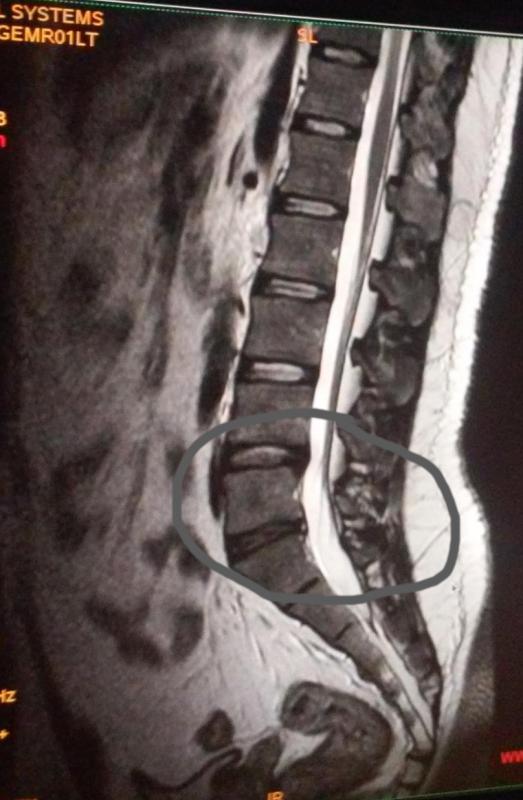

Huh suht keeruline seis siis. Sai ära käidud nädal tagasi MRT-s ning lõpuks sain teada siis, et mul on mingi diskide vahel rebend.

Muren oma pead nii, et jube sest paanikas ning ei oska edasi käituda trenniga… mida võib mida mitte? Või ikkagi unustada jõusaal absoluutselt.. nagu paljud ütlevad. Kiro siiani pole mul jõudnud pilte vaadata kuid ütleb, et jõusaaliga teed ainult karuteene omale. Homme peaks saama mingid harjutused mida lihtaslt teha kodus seljale, et see paranek. Lisaks 2x päevas Ibumetiin.

Kiro ütle, et ühest pildist ta ei loe midagi välja ja vaja seeriat, mis sai talle saadetud, programmis saad kõik kenasti läbi vaadata nagu live pildina. aga noh ta lihtsalt ei ole aega leidnud veel, et neid uurida.

Siin on üks pilt siis:

Lisasin veel ühe pildi kus näidatud ära joonisena, mis teema pm on